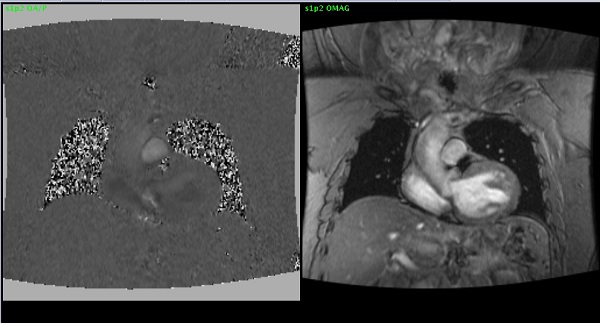

PC: with Cine mode scan

This PSD combines Phase Contrast and the Cine scan mode to enable data acquisition throughout the entire cardiac cycle. The RR Interval is monitored and the information is used to retrospectively sort the data before reconstruction. Images are reconstructed using CINE interpolation that compensates for differences within the cardiac cycle.

| 1 | Systole |

| 2 | Diastole |

| 3 | Phases |